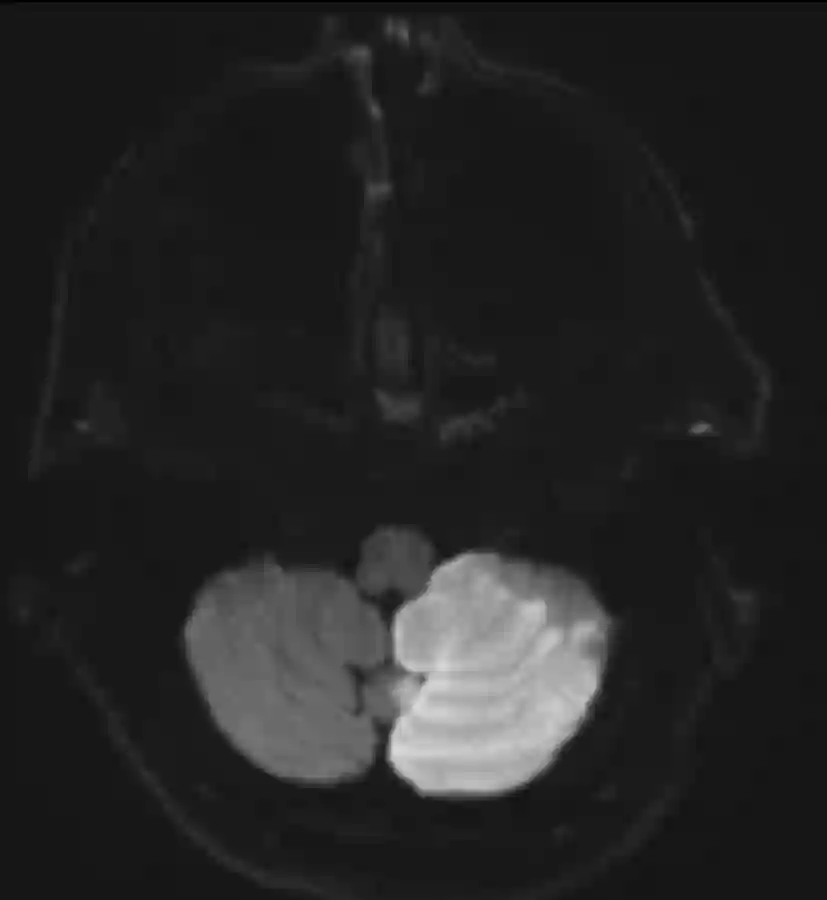

Linksseitiger PICA Infarkt im Kleinhirn im axialen MRI Bild.

Darstellung eines PICA Infarkts auf der linken Seite in einem axialen MRI Bild.